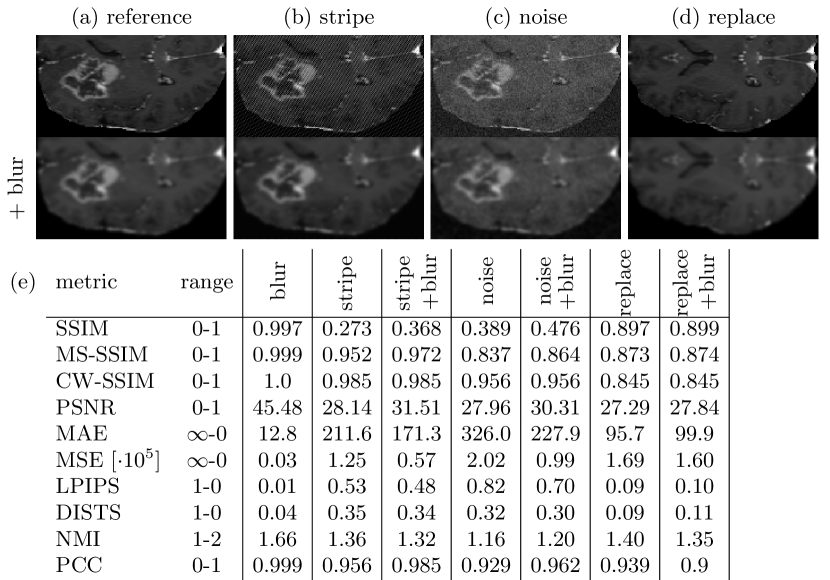

3.4 Pitfall 4: Error Metrics Prefer Blurred Images

When using loss functions based on error metrics, such as MSE, it has been reported and observed, that optimized models generate blurry images [18]. We assessed metric scores for three kinds of distortions and also for the undistorted images with additional blurring. We observe, that metric scores increase for the additionally blurred versions. The distortions are also perceived as weakened by the blurring. However, the overall quality and degree of blurriness is not satisfactory and we assume further blurring will not arbitrarily improve similarity. The metric score results and example images are shown in Fig. 4.

Refer to caption

Figure 4: An example region of interest with different distortions is shown in the first row: (a) reference, (b) stripes added, (c) Gaussian noise added, (d) lower half of the image replaced by mirror of the upper half. Mean similarity scores were assessed over 100 images (e). Blurring perceptually improves strong distortions and quantitatively improves most similarity scores, especially SSIM. Out of all observed metrics, NMI best detects blurring.